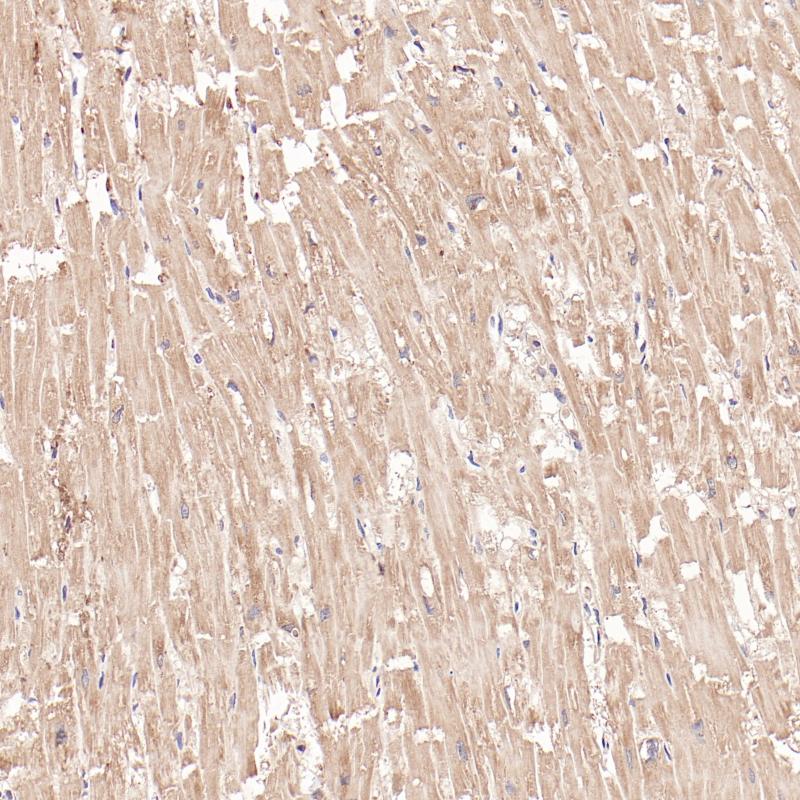

FABP3 重组兔单克隆抗体

阳性对照

心脏

亚细胞定位

细胞质